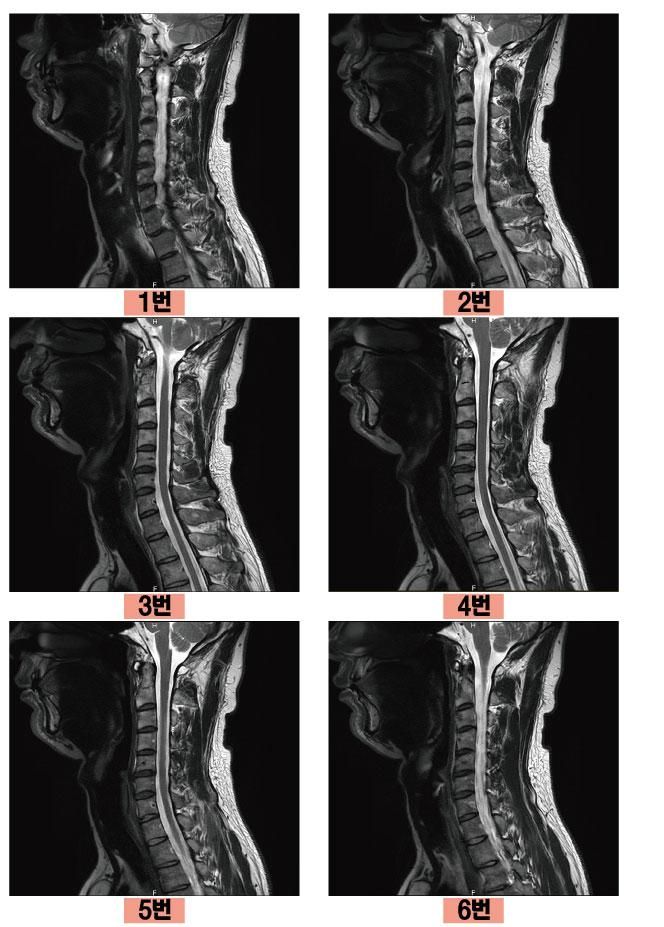

혹시 몰라서 경추와 흉추 MRI 를 찍은 사진을 올려봅니다.

번호 순서대로 휠을 굴렸을 때의 사진 양상인데요

척추병원마다도 소견이 다 달라서 공통적인건 경추 5,6번에 퇴행성 진행이 좀 보이고 초기 목디스크 정도이고 충분히 나을 수 있는 상태라며 흉추는 문제없다고 하고 그럽니다. 근데 어떤 의사분은 3,4번에도 약간 문제가 있어보인다는 분이 한 분 계셨는데 다른 분들은 거기에 대한 언급은 없었습니다.

• 1번 째 사진

• 2번 째 사진

• 3번 째 사진